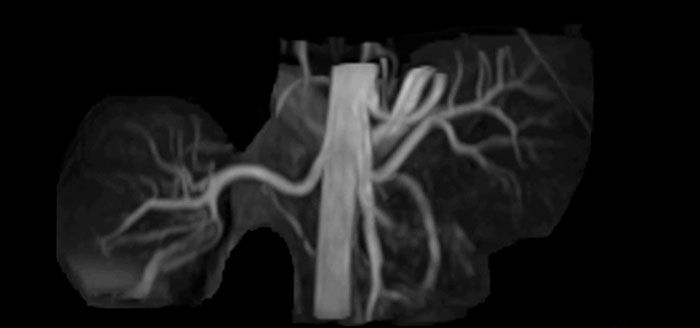

Non-contrast MRA of renal arteries

Imaging the renal arteries without contrast agent on Prodiva 1.5T.

TRANCE MIP

eMIP native Angio RL

“The quality of the contrast-free MR angiography keeps impressing us,” says Mrs. Schiffer. “In addition to not having to inject contrast agent, these images are amazing, for instance of the carotids. Also our exams of shoulders and hands are really exceptional. Images of the hands, for example, cover the fingertips and include the full wrist as well, all with high signal-to-noise ratio.”